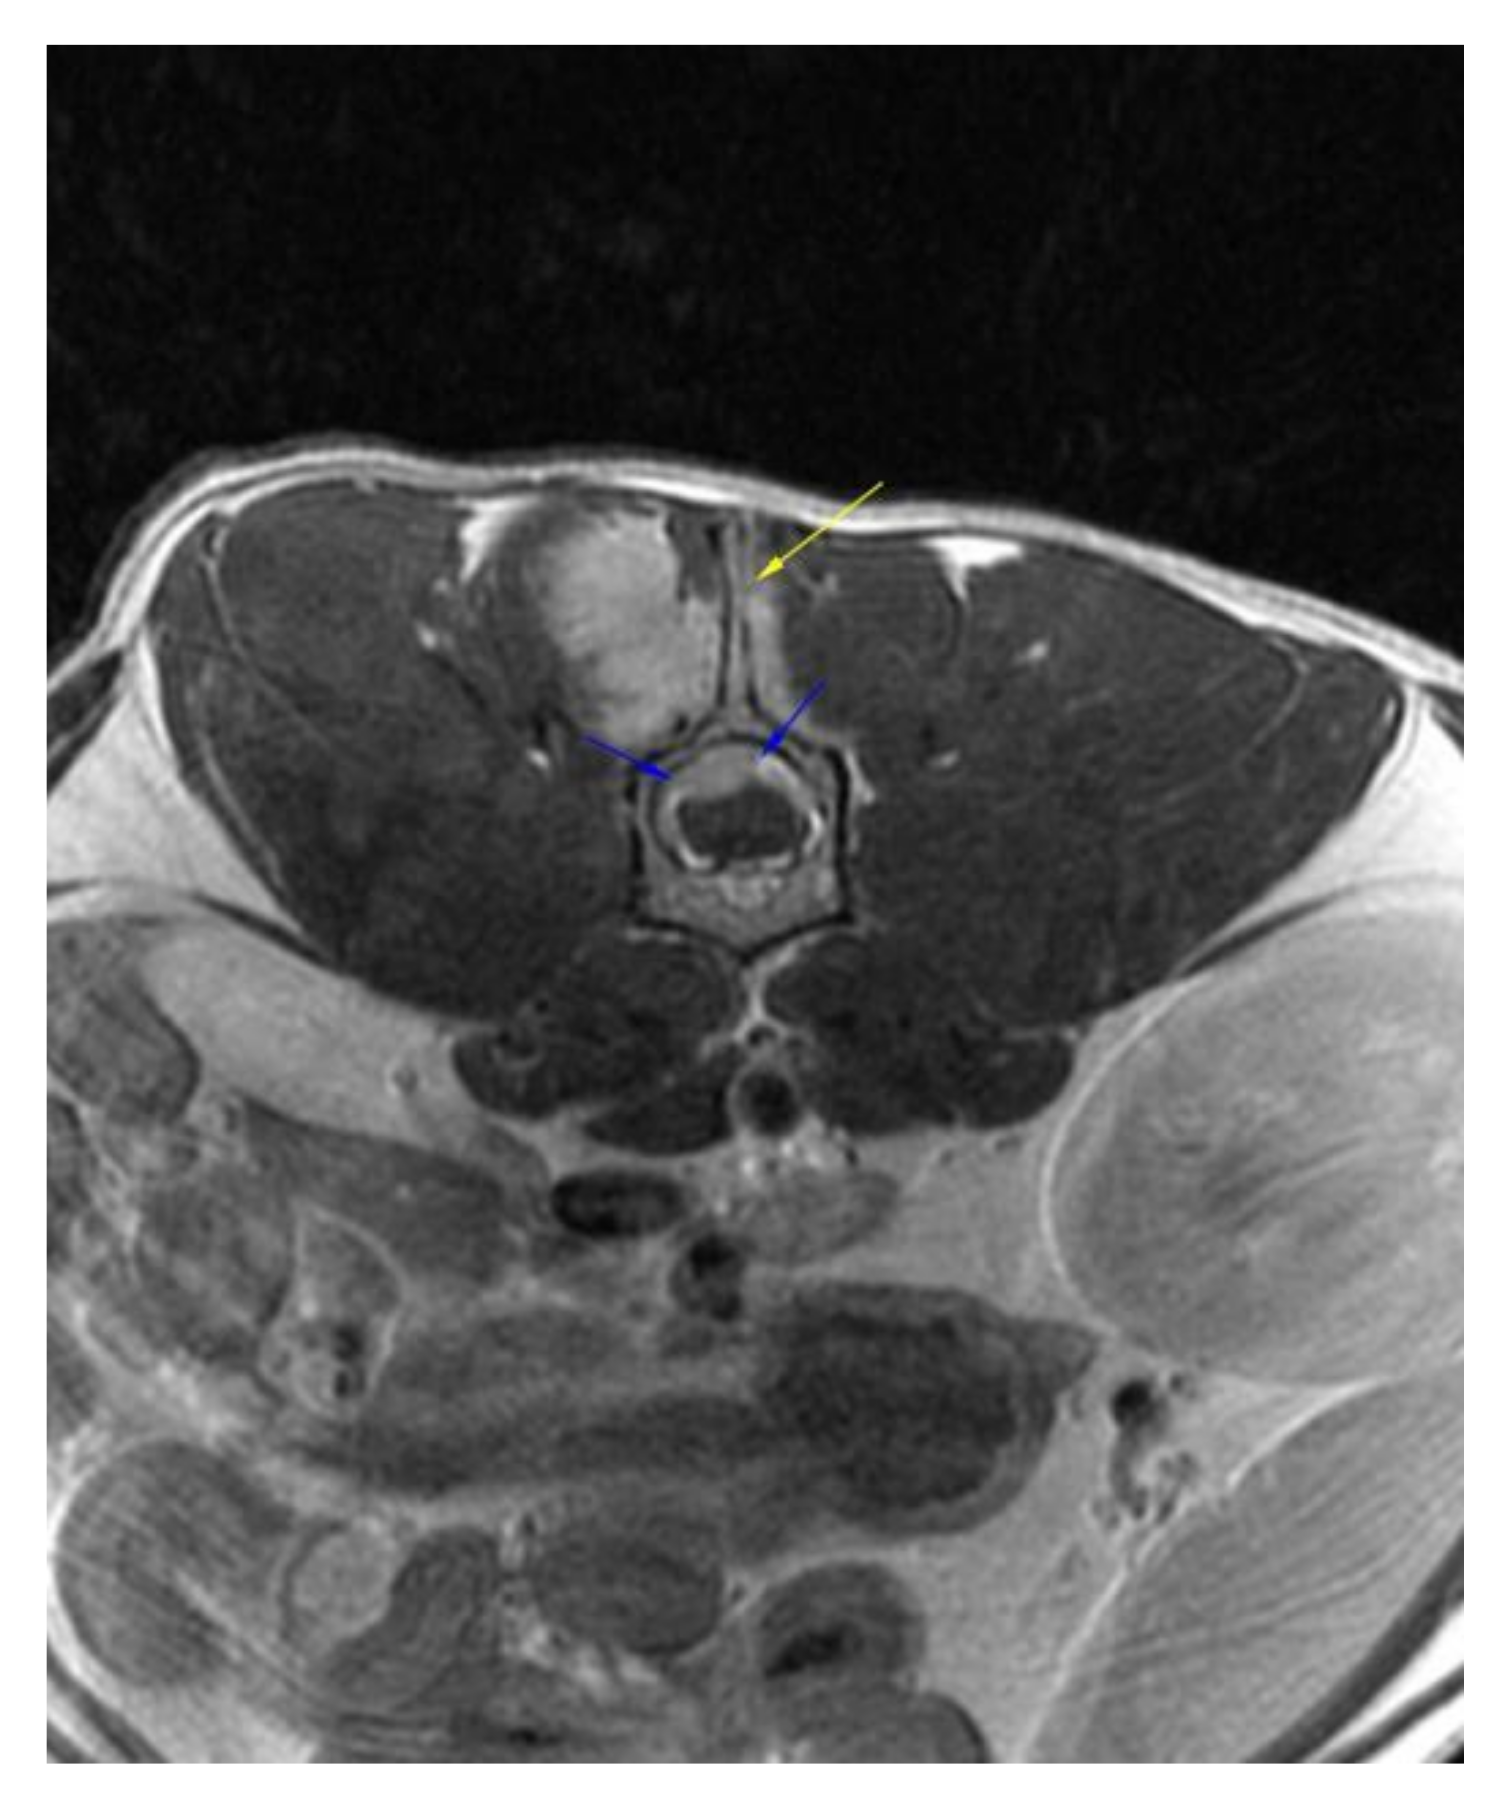

:1. Case Description

2. Materials and Methods

3. Results